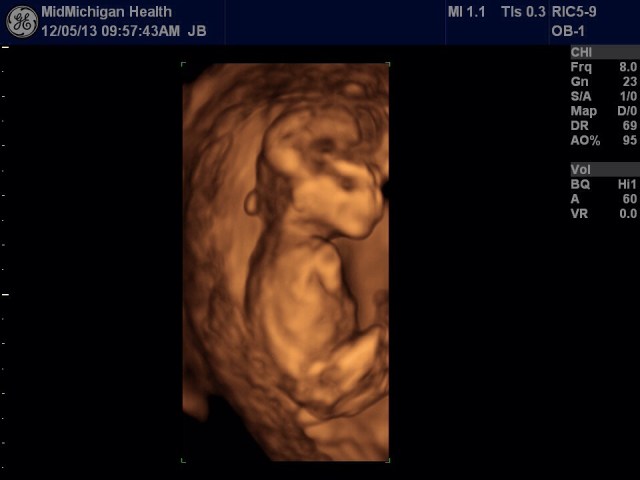

But today, my heart is so very full of thanks for this beautiful baby.

My daughter and her husband had their first ultrasound today. Baby Q is due in June.

That makes two grand babies in one year as my son and his wife are due on Valentines Day.